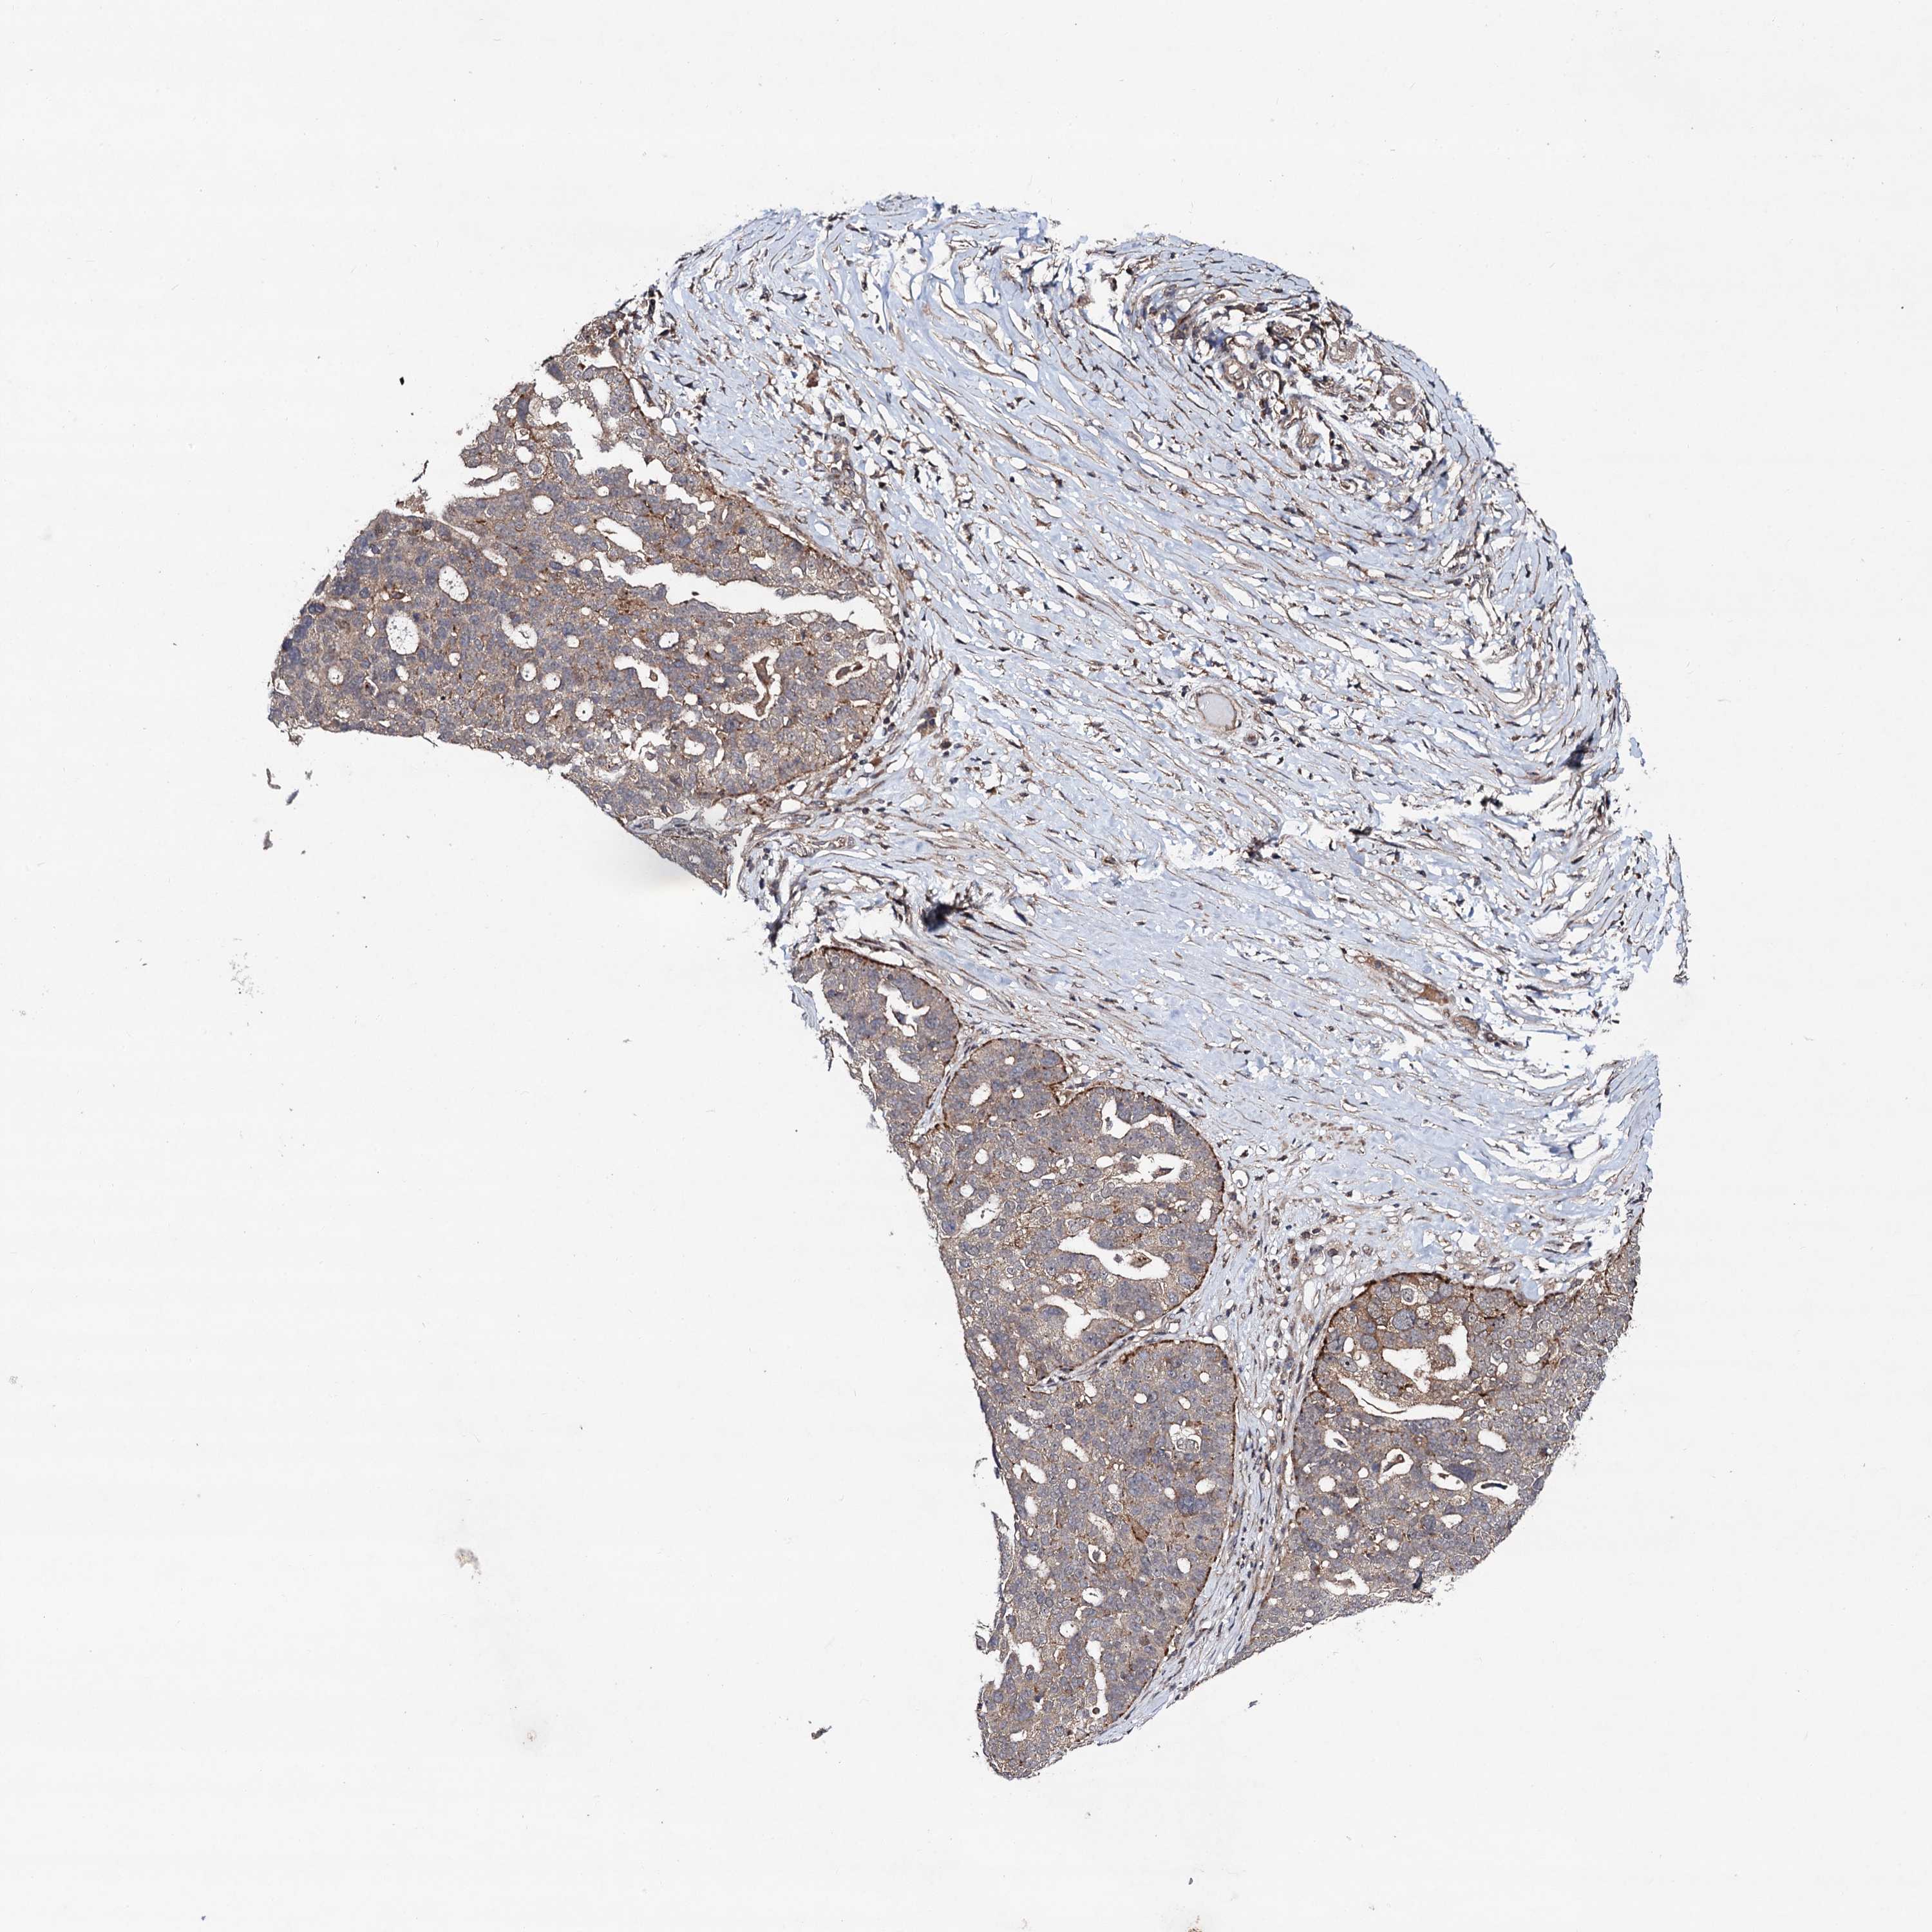

OVARIAN CANCER - Protein expressioni

A mouse-over function shows sample information and annotation data. Click on an image to view it in a full screen mode. Samples can be filtered based on level of antibody staining by selecting one or several of the following categories: high, medium, low and not detected. The assay and annotation is described here.

Note that samples used for immunohistochemistry by the Human Protein Atlas do not correspond to samples in the TCGA dataset.

Antibody stainingi

Antibody staining in the annotated cell types in the current human tissue is reported as not detected, low, medium, or high, based on conventional immunohistochemistry profiling in selected tissues. This score is based on the combination of the staining intensity and fraction of stained cells.

Each image is clickable and will lead to virtual microscopy that enables deeper exploration of all samples and also displays staining intensity scores, fraction scores and subcellular localization as well as patient and tissue information for each sample.

Antibody HPA041507

Antibody HPA041599

Cystadenocarcinoma, serous, NOS

Carcinoma, endometroid

Cystadenocarcinoma, mucinous, NOS

Carcinoma, NOS